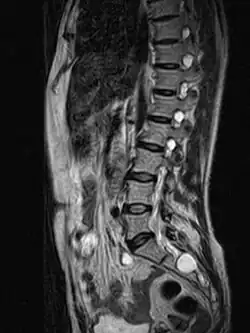

| MRI image showing a Tarlov cyst | |

MRI

MRI, or Magnetic Resonance Imaging, is considered the imaging study of choice in identifying Tarlov cysts. MRI provides better resolution of tissue density, absence of bone interference, multiplanar capabilities, and is noninvasive. Plain films may show bony erosion of the spinal canal or of the sacral foramina. On MRI pictures, the signal is the same as the CSF one.